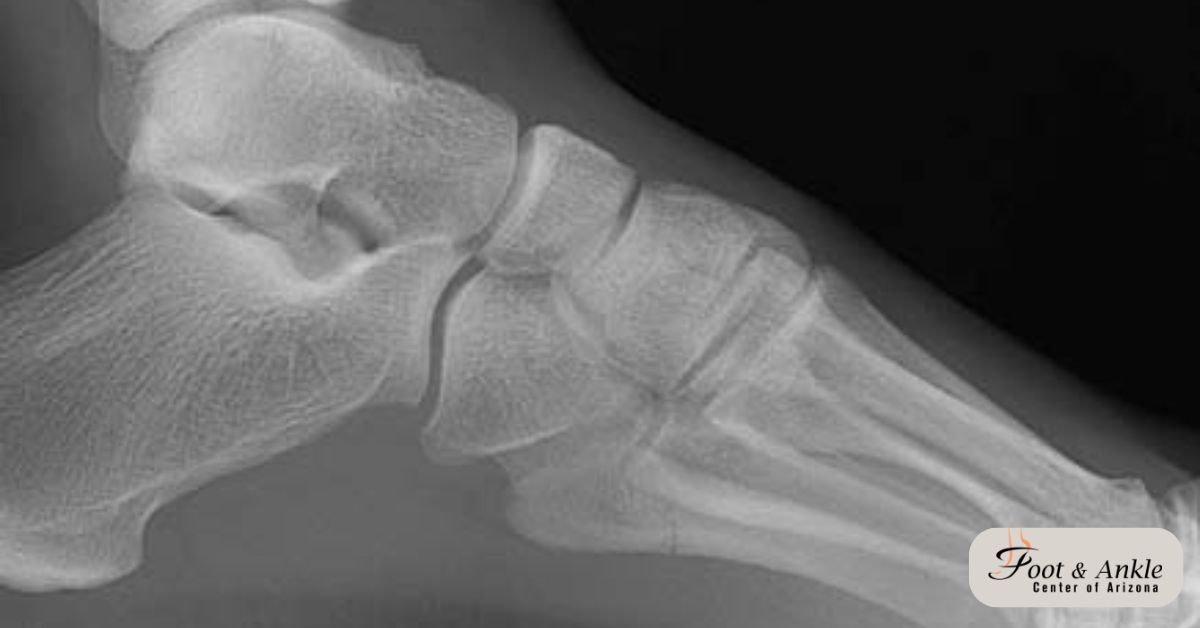

Although hammertoes are readily apparent, to arrive at a diagnosis the foot and ankle surgeon will obtain a thorough history of your symptoms and examine your foot. During the physical examination, the doctor may attempt to reproduce your symptoms by manipulating your foot and will study the contractures of the toes. In addition, the foot and ankle surgeon may take x-rays to determine the degree of the deformities and assess any changes that may have occurred.